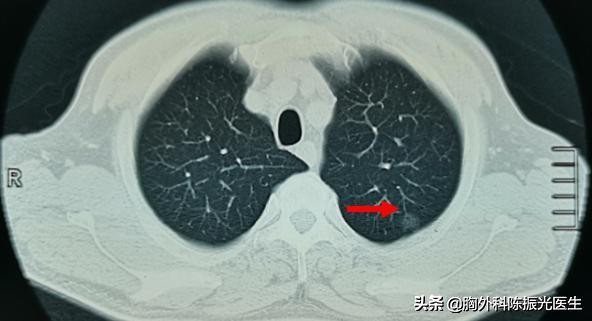

张女士是第三次来我这了,2017年做CT发现左肺下叶有一个6mm左右的肺磨砂玻璃结节,随访建议定期复查胸部CT。今年的检查虽然这个结节的大小和形态并没有变化。但是在片子上我发现这个结节有一定程度上的密度变化,有由磨砂玻璃结节转变为半实性结节的倾向。

有些肺磨砂玻璃结节,经过1~2年或者2~3年随访观察,它的大小并没有变化,但是它的密度增加了,实际上这也是提示磨砂玻璃结节是恶性的可能性较大。因为恶性磨砂玻璃结节在生长过程中,主要表现结节的密度增加较明显,而大小改变不明显。

如果是磨砂玻璃结节均匀地转变成实性结节,那么只需要观察就可以了,不需要太过紧张;如果是磨砂玻璃结节不均匀地出现实性成分,实性部分和磨砂玻璃部分呈现一定比例,这时候应当注意了,可能是癌变。

肺磨砂玻璃结节一年左右复查,CT值(代表结节密)增加了100HU以上,考虑原位癌、微浸润腺癌等恶性病灶可能性较大,需行积极的外科手术治疗。